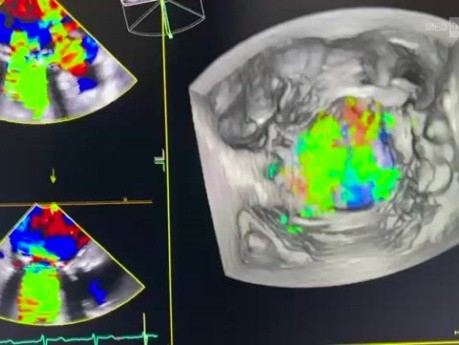

Duży przeciek okołozastawkowy wokół mechanicznej...

Ten film przedstawia duży przeciek okołozastawkowy wokół mechanicznej zastawki mitralnej.